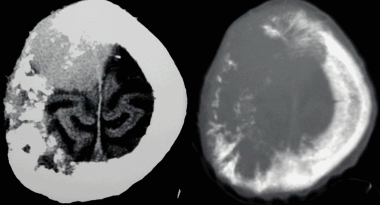

Анапластическая менингиома лобной доли. Н а КТ-изображении в режиме мозгового окна и костного окна Хаунсфильда видна крупная внутрикостная менингиома. Обнаруживаемые КТ-феномены неспецифичны и могут включать различные изменения от остеолиза до остеосклероза. Внутрикостные менингиомы составляют менее 1% опухолей костной ткани.